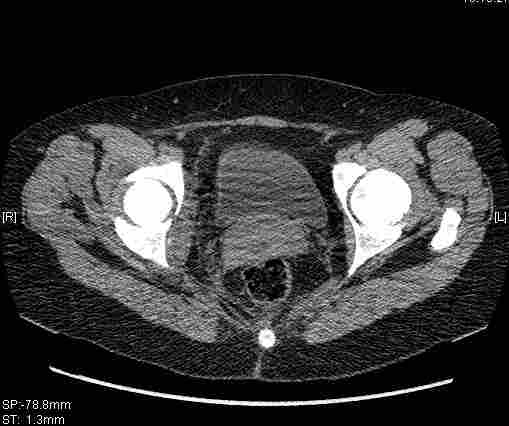

Удалось сегодня вывести пациентку в соседнюю больницу, где есть кт. Срезы сделаны только горизонтальные.